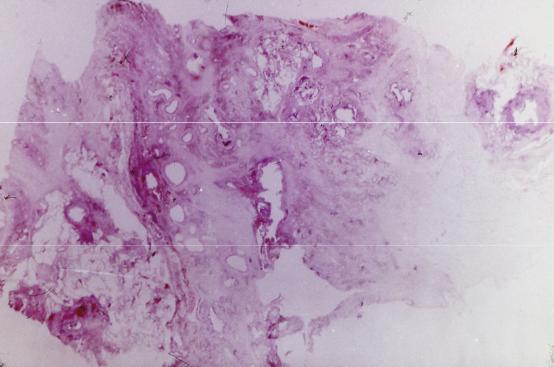

Микроскопический взгляд на мишитарный туберкулез легкого: фотодокументация